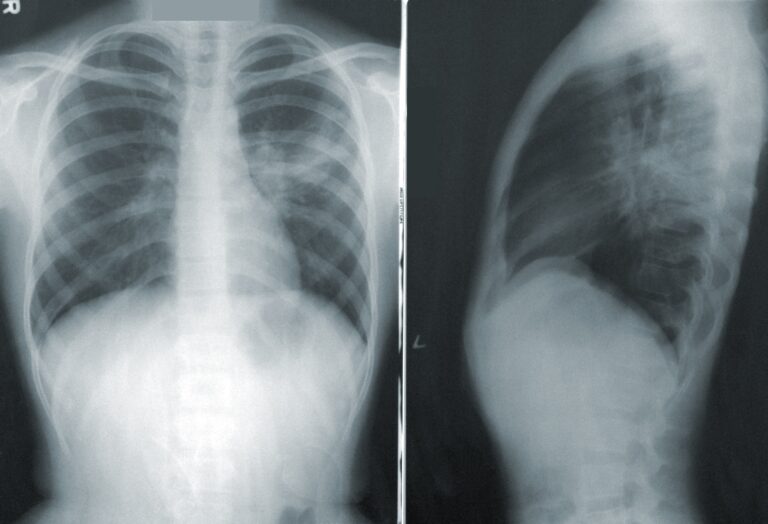

chest x-rayLa radiografía de tórax es una prueba de diagnóstico por imagen que permite obtener una imagen de los órganos del tórax, como los pulmones, el corazón y los vasos sanguíneos. Esta prueba se realiza utilizando una máquina de rayos X que emite una pequeña cantidad de radiación ionizante para obtener imágenes del interior del cuerpo. La radiografía de tórax es una herramienta diagnóstica muy útil que se utiliza para detectar una amplia variedad de enfermedades y trastornos.

La radiografía de tórax es una prueba no invasiva y segura que se realiza en una sala especializada en radiología. Durante la prueba, el paciente se coloca de pie frente a una placa de rayos X y se le pide que mantenga una posición específica mientras se toman las imágenes. El técnico de radiología puede colocar al paciente en diferentes posiciones para obtener imágenes de diferentes ángulos.